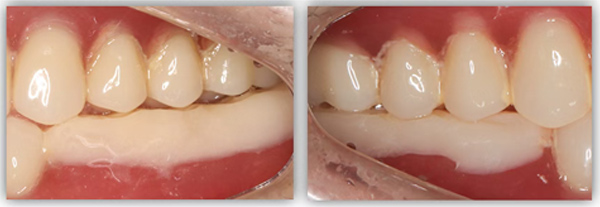

为满足患者的需求,我为她制订了一个即拔即种、种植后早期负重的方案,把五个治疗步骤缩减为三步。首次来院时,我为她完成了拔牙、种牙和安装基台,6周后来院拆线和取模,两周后完成牙冠修复,也就是戴牙。整个治疗周期仅8周,不到两个月就完成了。

6号牙也就是第一磨牙,是最早萌出的恒牙,比较容易龋坏。它虽然不在前牙美学区,不太容易影响容貌,但出于对美学的高要求,我在设计方案时也考虑了是按常规流程先拔牙,再备洞,还是以修复为导向,先按现有的牙冠来确定未来修复体的形状,再去反推种植体植入的位置。后者对医生来说难度更高一些,但更有利于复原天然牙的形态。

为保证这个方案的顺利实施,我通过查阅文献去印证方案的可行性,还为她建议了适合的种植体,原来三个月的骨结合时间能缩短为两个月,种植体功不可没。